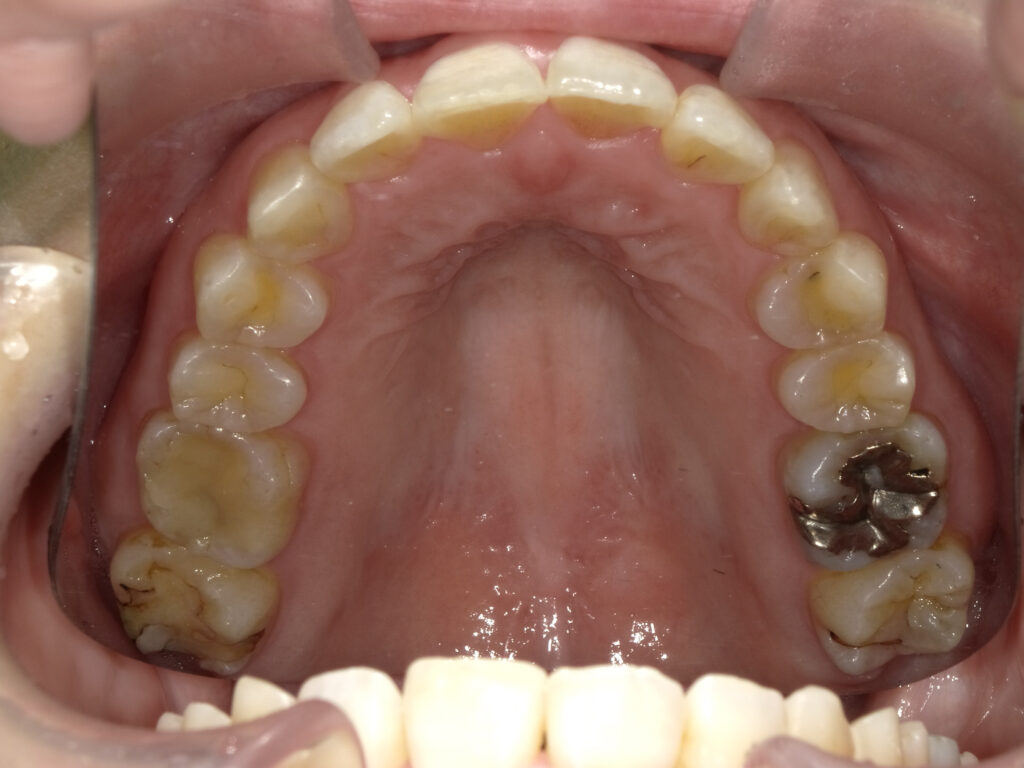

上顎

治療前

治療後